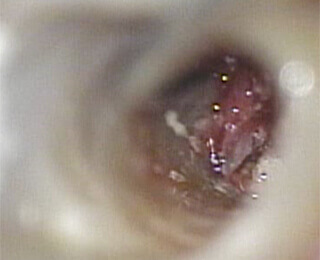

8

拡大すると見逃していた神経が現れ膿が出てきました。そこを綺麗にすると疼いていた症状が無くなりました。